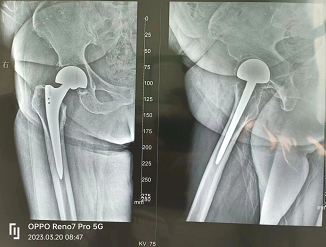

老年髋部骨折的典型术式——髋关节置换

半髋关节置换

全髋关节置换